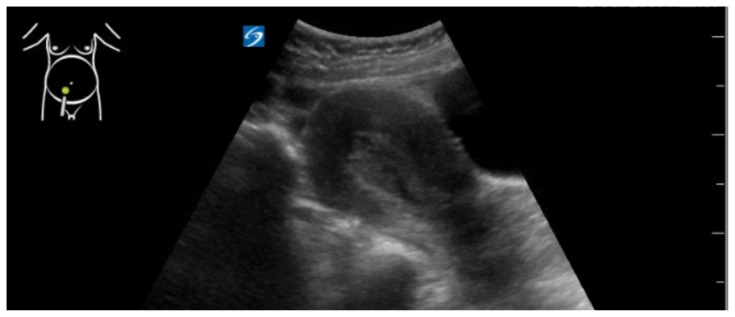

Abstract Image